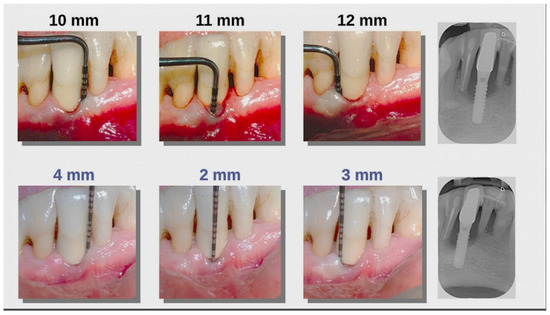

6.2. Clinical Results

| CAL (Mean ± SD) | PD (Mean ± SD) | p Value | |

|---|---|---|---|

| SRP (20 sites) | 4.08 ± 0.44 | 4.73 ± 0.34 | <0.00001 * |

| SRP plus Aladent (20 sites) | 2.42 ± 0.46 | 2.87 ± 0.43 | <0.00001 * |